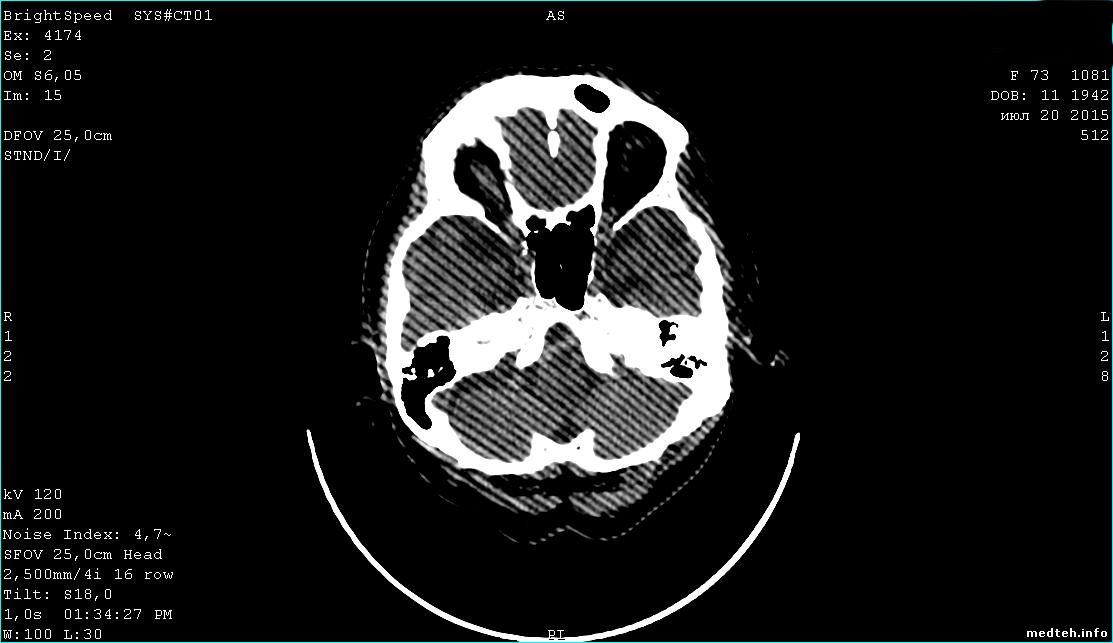

Здравствуйте коллеги!!! Хотел бы поинтересоваться с проблемой КТ GE BrightSpeed Elite 16. На снимке редко но иногда появляются артефакты в виде полос под наклоном (фото прилагаю), и именно когда происходит исследование головной части при наклоне угла гентри примерно 13 градусов. Остальные исследования идут нормально. Склоняюсь, что ковырять надо в настройках протоколов...хотя не уверен. Подскажите что можно еще проверить тк видимых причин нету. И еще, какая должна быть температура помещения когда работает КТ. Спасибо.

6435916.jpg (199.6 Kb)